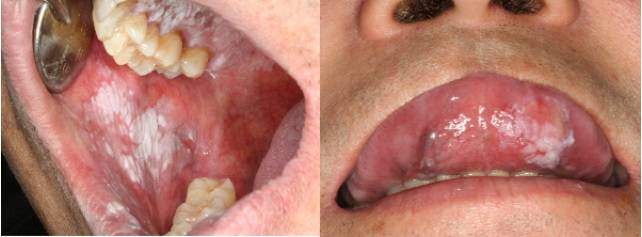

구강암을 의심할 수 있는 증상은 3주 이상 낫지 않는 궤양, 입안 부기, 삼키기 힘든 증상, 목에 만져지는 혹, 6주 이상 지속되는 목소리 변화와 구강 점막에 생긴 적색·백색 반점<사진 참조> 이다. 사진>

구강암을 의심할 수 있는 증상은 3주 이상 낫지 않는 궤양, 입안 부기, 삼키기 힘든 증상, 목에 만져지는 혹, 6주 이상 지속되는 목소리 변화와 구강 점막에 생긴 적색·백색 반점<사진 참조>이다. 잇몸질환과 무관하게 치아가 흔들리는데 원인을 찾기 어렵거나, 한쪽 코가 지속적으로 막혀 있는 것도 구강암 신호일 수 있다. 특히 입안에 생긴 궤양이 3주 이상 지속되면 병원을 찾아야 한다. 일반적인 구내염은 일주일에서 열흘이면 사라진다.